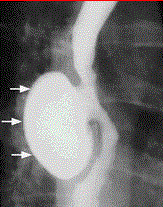

问题 患者男,54岁,近2年来有胸骨后疼痛感,饮食睡眠情况可,体重未减轻,行X线钡餐检查,结果如下图。最有可能的诊断是

选项 A、贲门失弛缓症 B、食管裂孔疝 C、食管平滑肌瘤 D、食管憩室 E、食管癌

答案 D